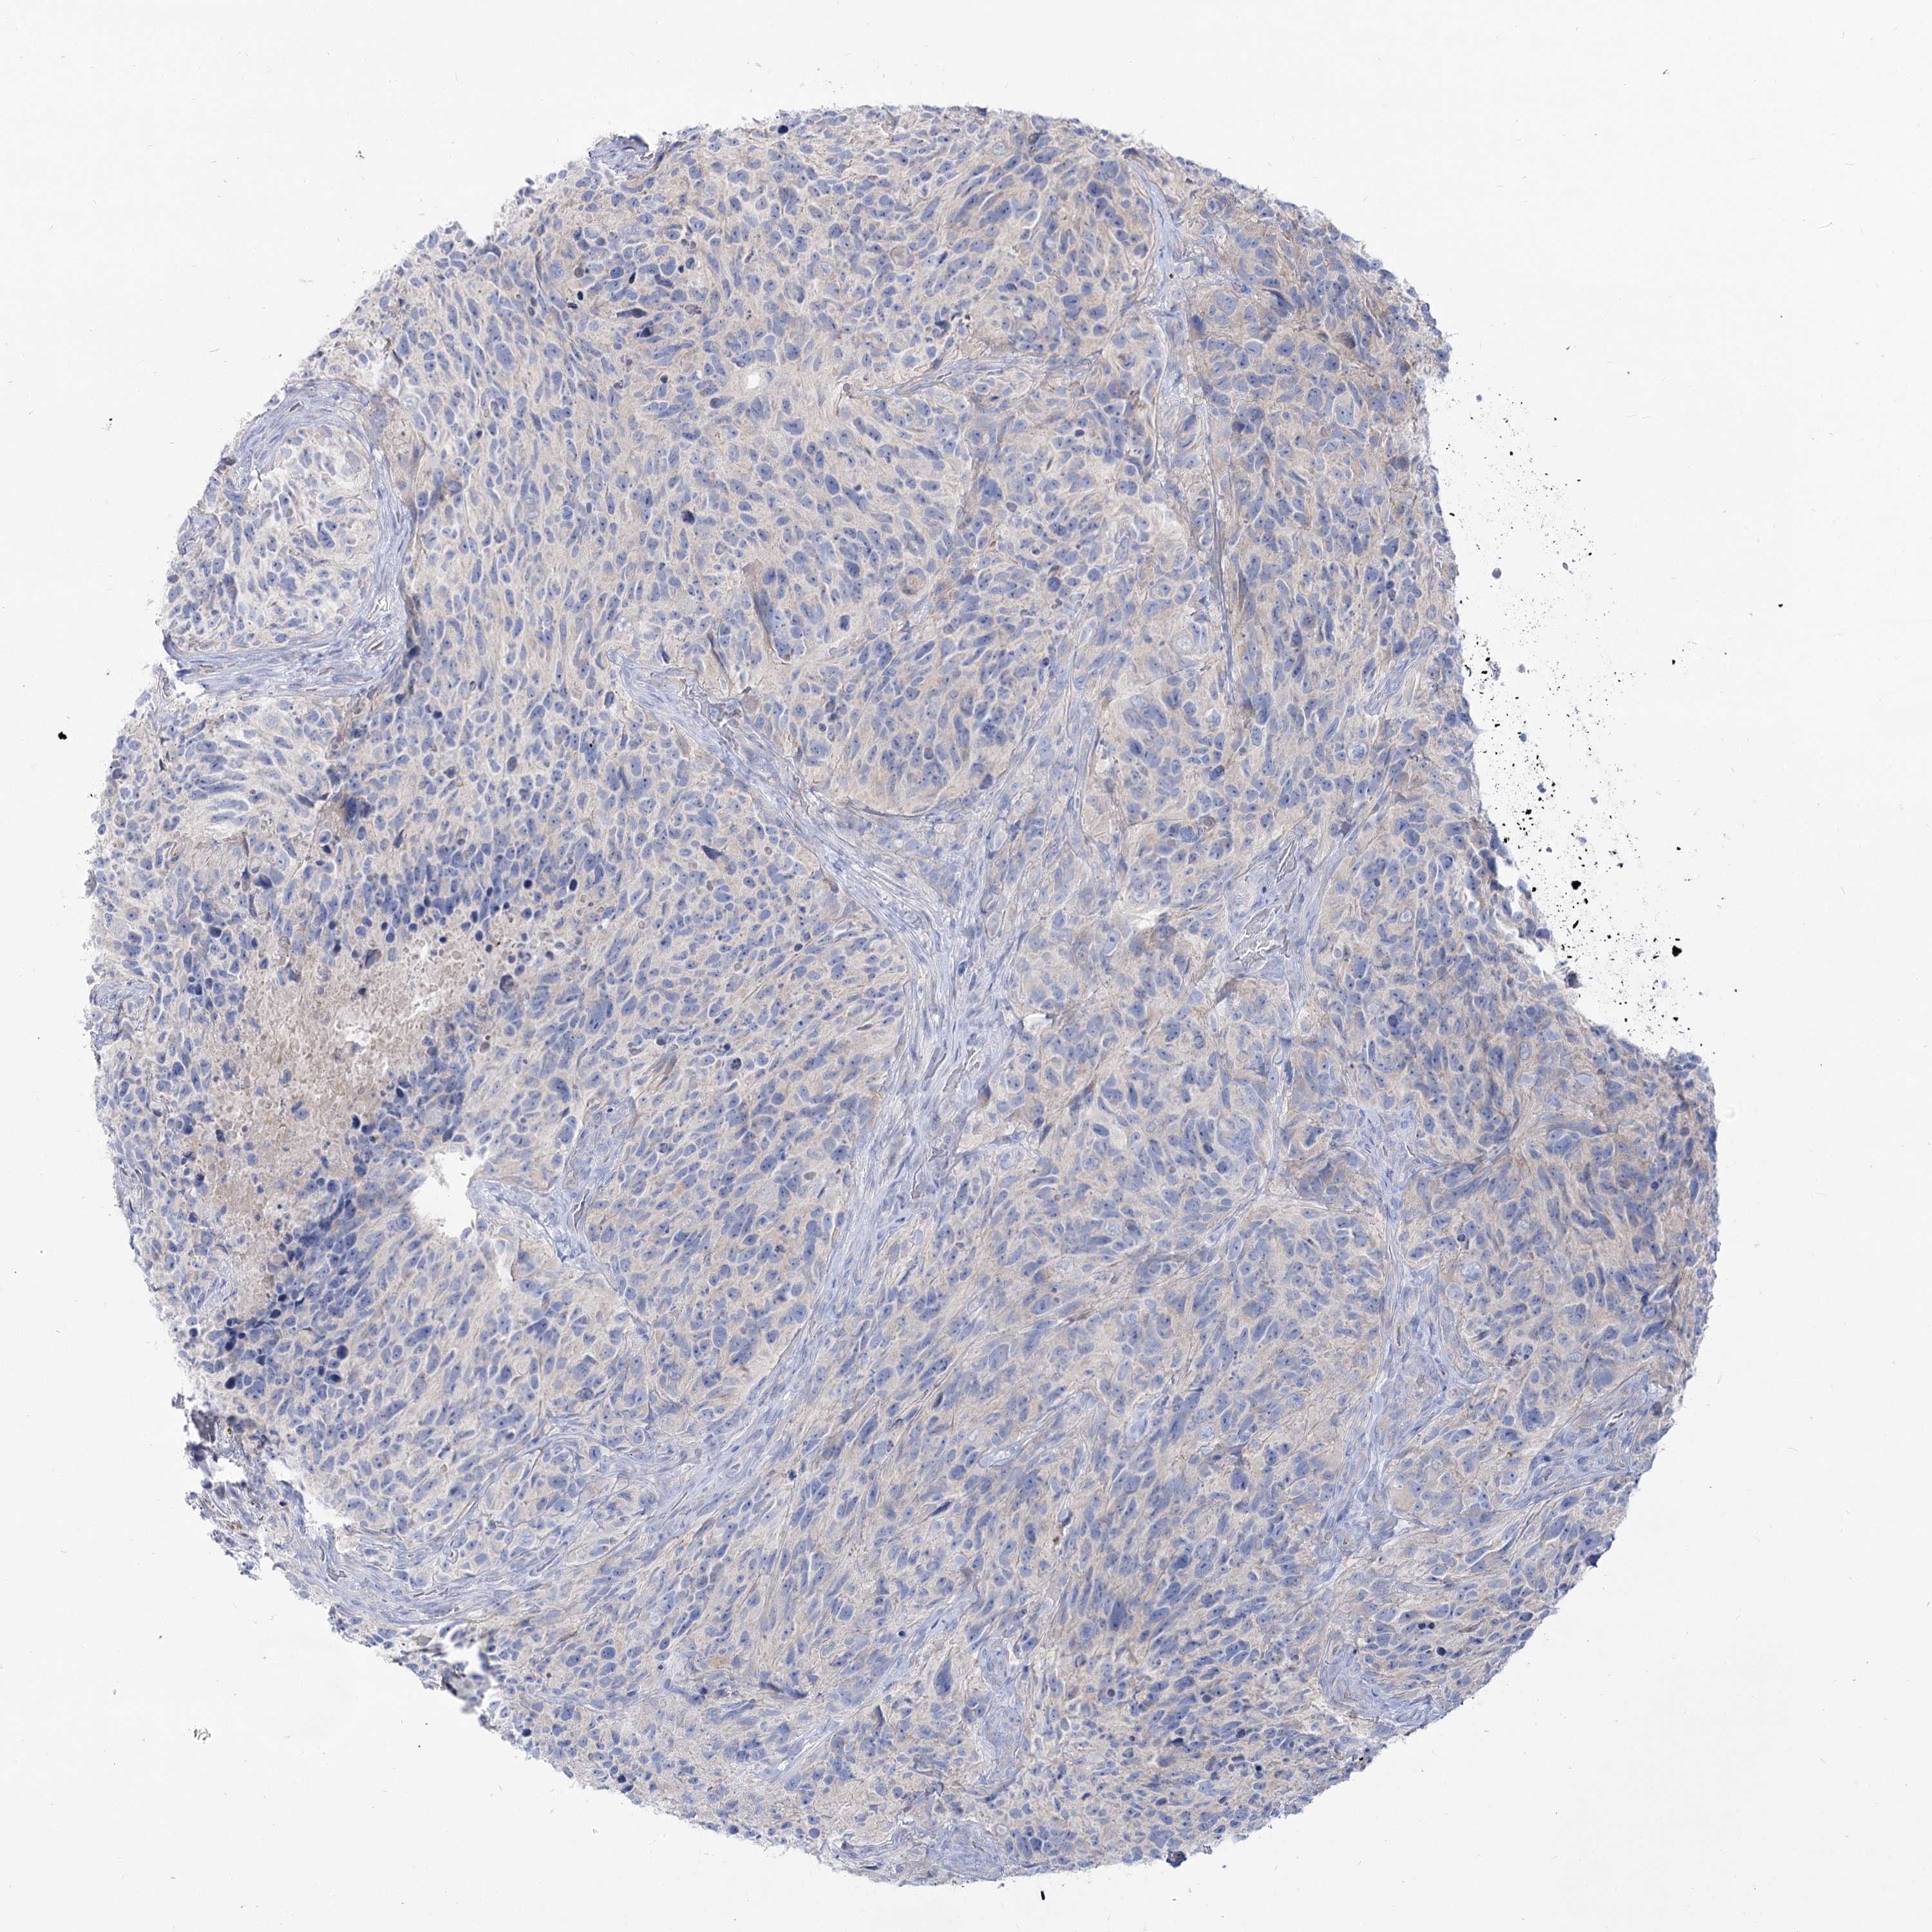

GLIOMA - Protein expressioni

A mouse-over function shows sample information and annotation data. Click on an image to view it in a full screen mode. Samples can be filtered based on level of antibody staining by selecting one or several of the following categories: high, medium, low and not detected. The assay and annotation is described here.

Note that samples used for immunohistochemistry by the Human Protein Atlas do not correspond to samples in the TCGA dataset.

Antibody stainingi

Antibody staining in the annotated cell types in the current human tissue is reported as not detected, low, medium, or high, based on conventional immunohistochemistry profiling in selected tissues. This score is based on the combination of the staining intensity and fraction of stained cells.

Each image is clickable and will lead to virtual microscopy that enables deeper exploration of all samples and also displays staining intensity scores, fraction scores and subcellular localization as well as patient and tissue information for each sample.

Antibody HPA038208

Antibody HPA038209

Staining

High

Medium

Low

Not detected

Intensity

Strong

Moderate

Weak

Negative

Quantity

>75%

75%-25%

<25%

None

Location

Nuclear

Cytoplasmic/membranous

Cytoplasmic/membranous,nuclear

Glioma, malignant, High grade

Glioma, malignant, Low grade

Glioblastoma, NOS